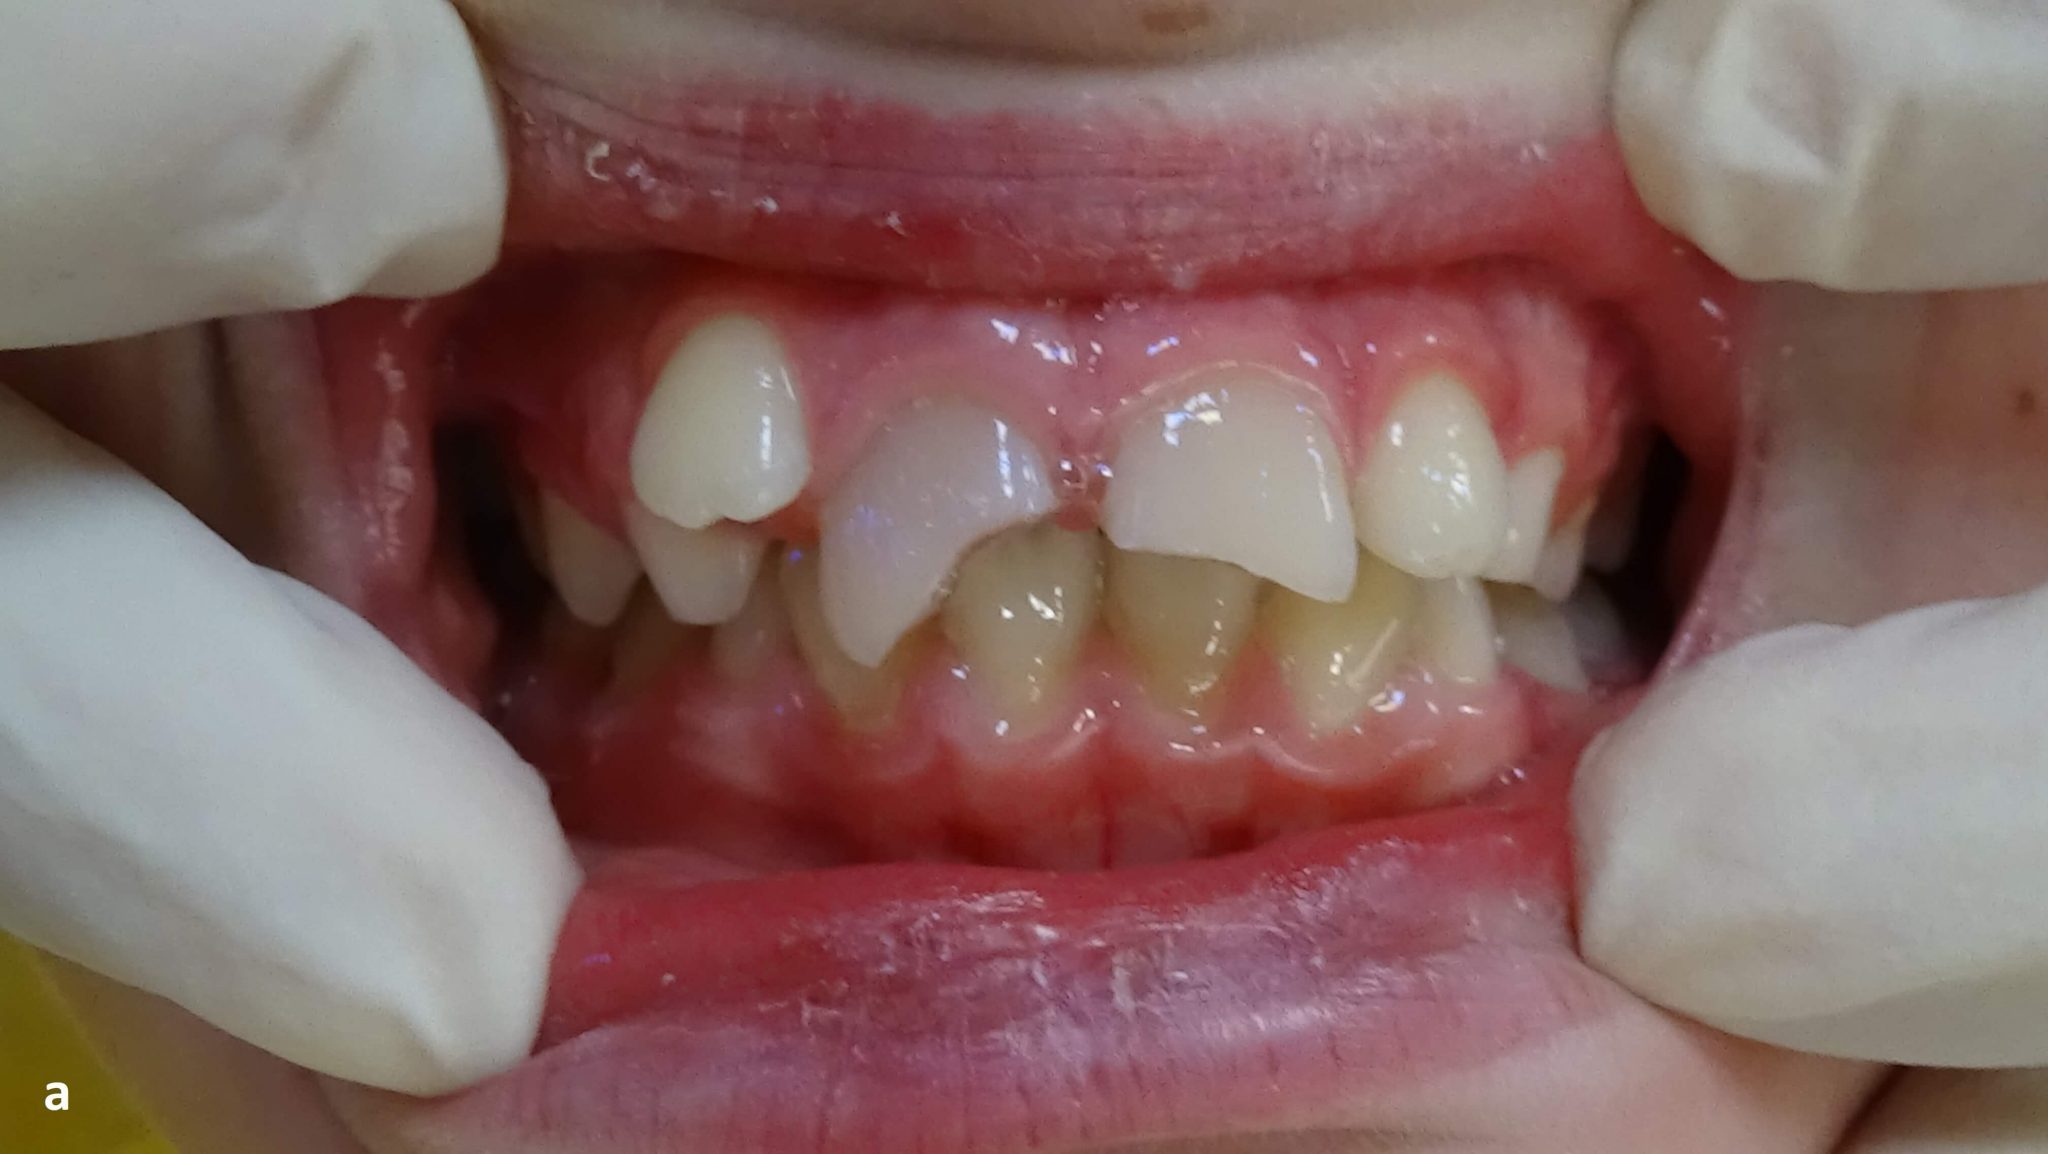

From www.orisdentalcenter.ae

What Is Meant by Overjet Teeth? Oris Dental Center Increased Overjet Dental Trauma An increased overjet of 6 mm. Specifically, the review will elucidate the critical level, in millimetres, at which an overjet will place an individual at an increased. An increased overjet of 6 mm or more had. In this prospective study, overjet stood out among variables as the most significant risk factor of tdi: The objective of this review of association. Increased Overjet Dental Trauma.